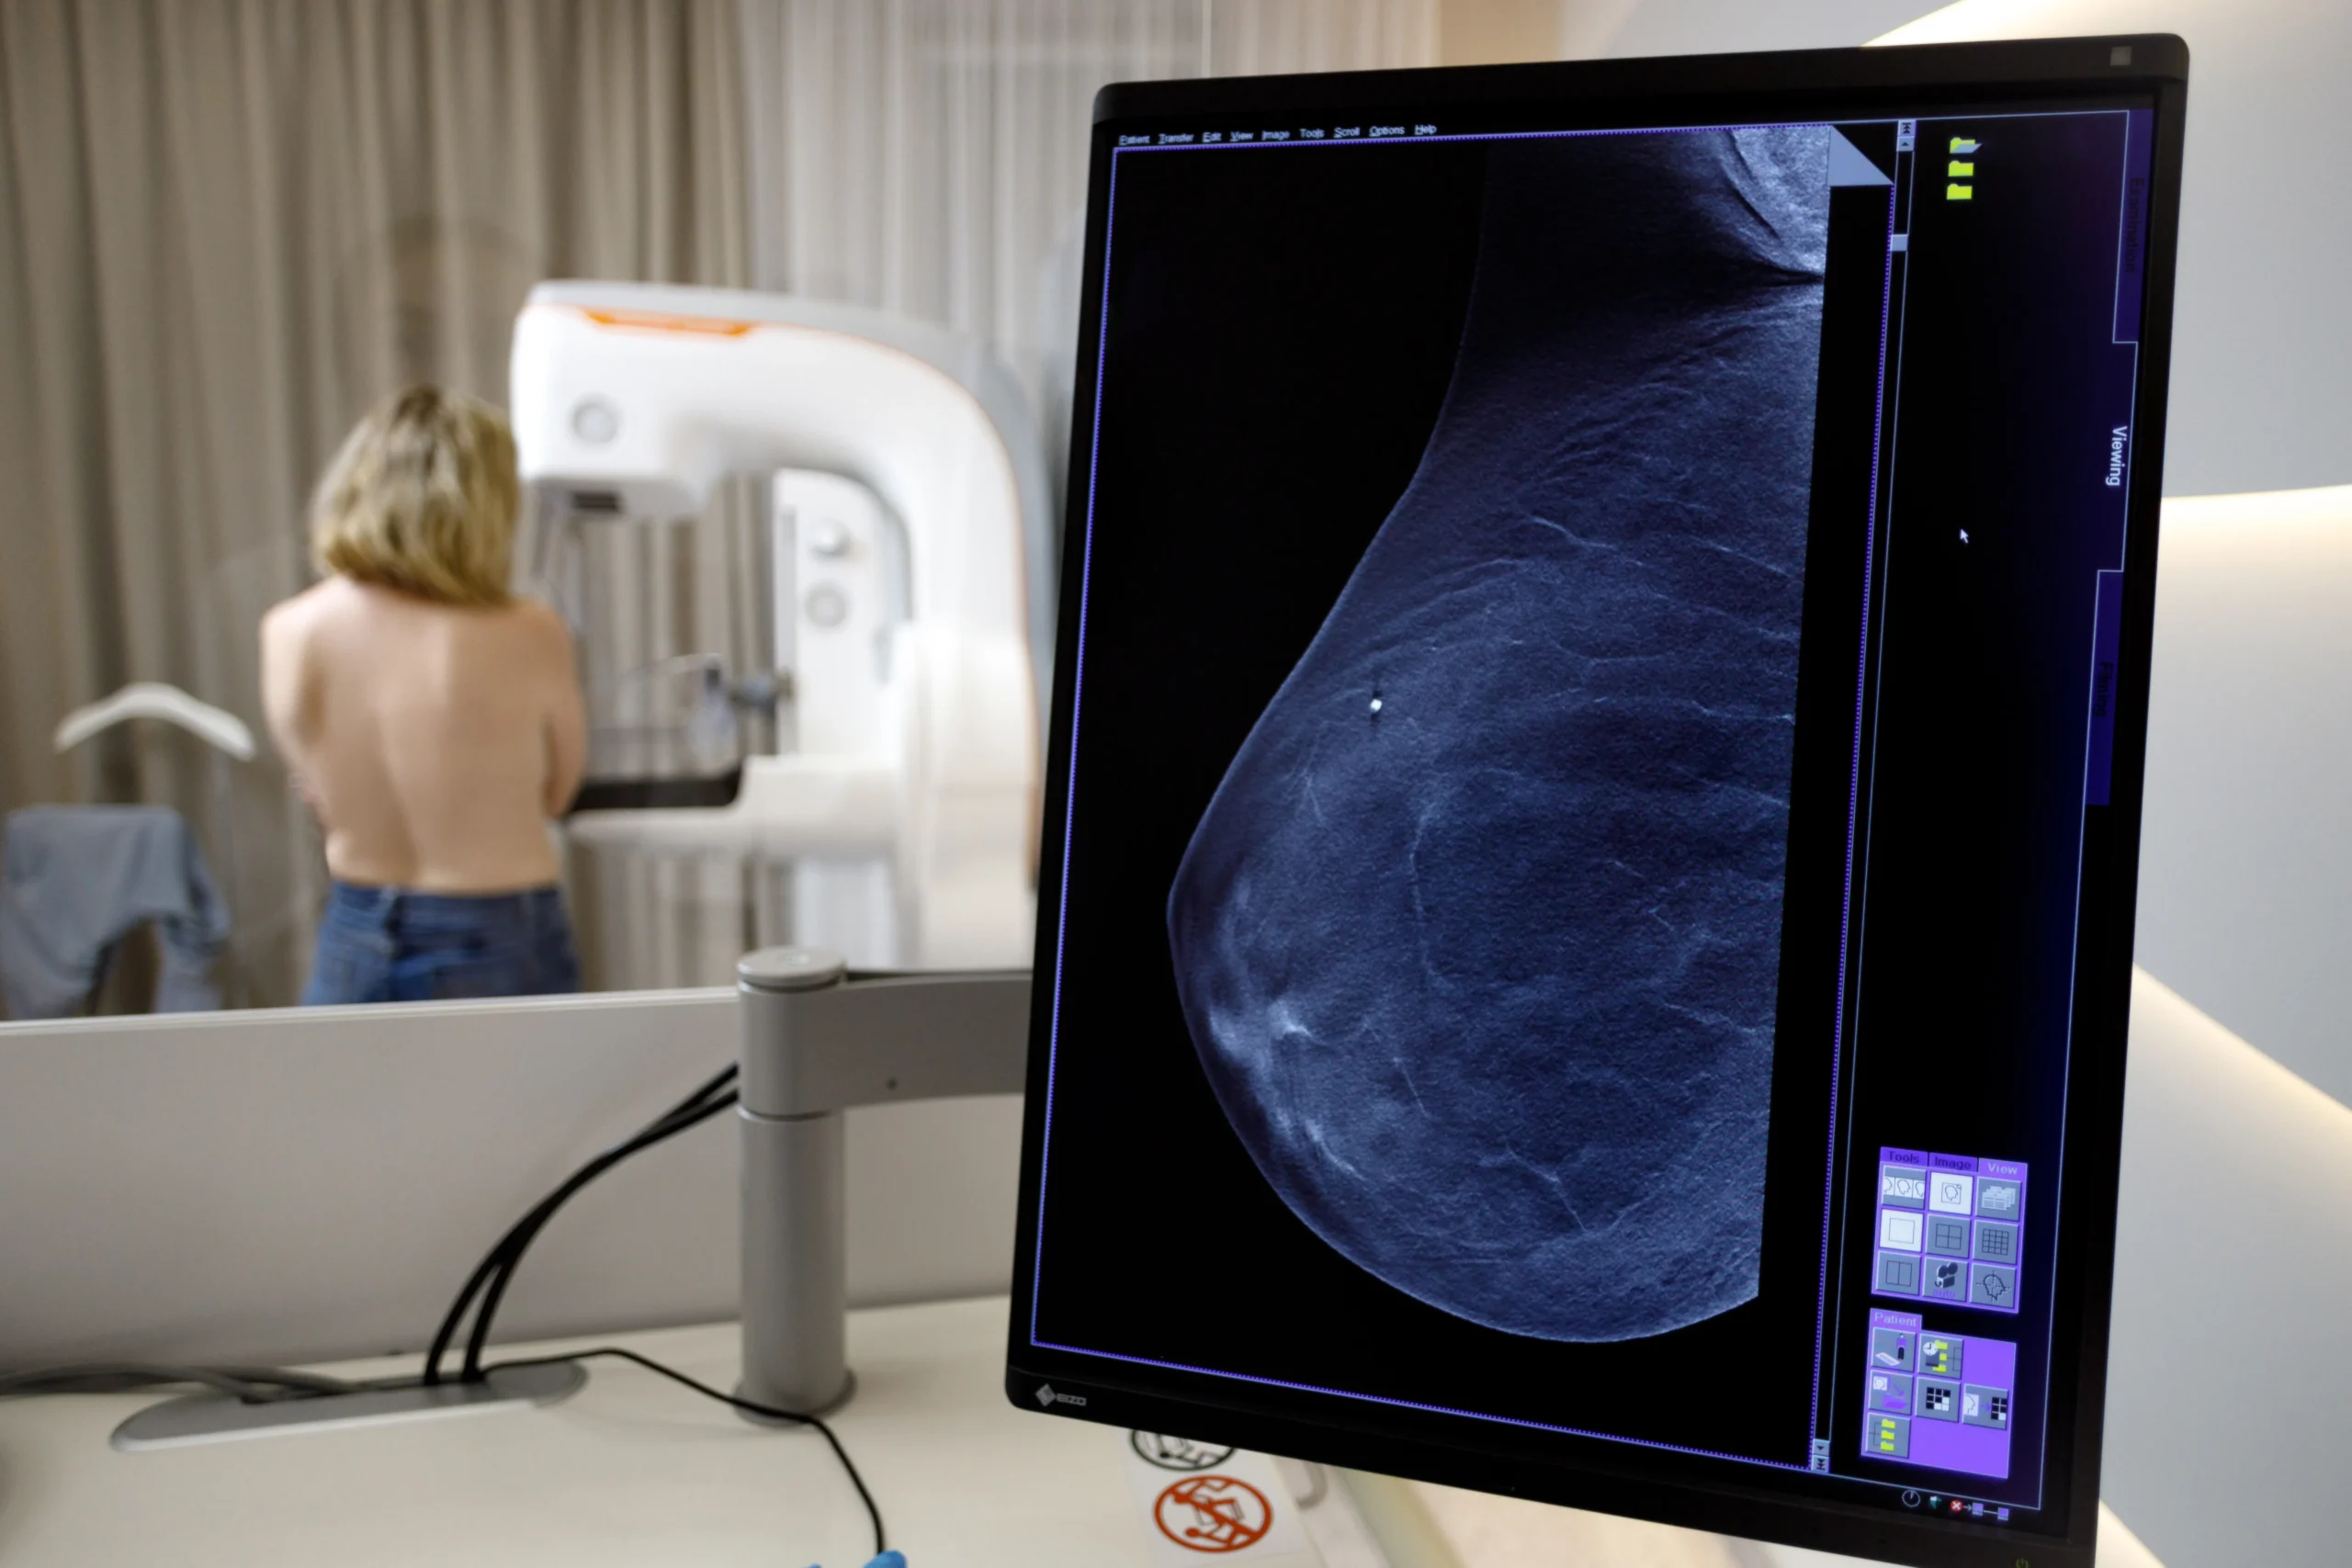

Щорічний профілактичний огляд є ключем до виявлення патологій грудей на ранніх стадіях. Мамографія в медичному центрі «Асклепій» — це рентгенологічне дослідження, що дозволяє з високою точністю виявити злоякісні та доброякісні зміни у тканинах молочної залози. Це найважливіший скринінговий метод для жінок, особливо після 40 років.

🔹ми використовуємо сучасне обладнання з мінімальною дозою опромінення, що гарантує чіткість знімків і безпеку.

🔹ваші знімки аналізують досвідчені фахівці, що забезпечує своєчасне виявлення навіть найменших змін.